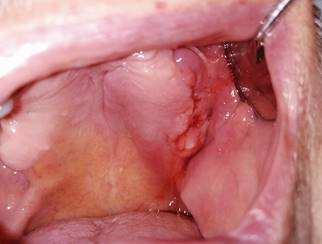

Fig. 2: Vista intraoral de lesión en el lado izquierdo del maxilar con salida de contenido hemático e inflamación de los tejidos circundantes

Al examen clínico en una primera instancia no se observó asimetrías ni aumento de volumen en región facial (Fig. 1). A nivel intraoral, se observó desdentamiento total superior con presencia de una disrupción de continuidad lineal a nivel de la mucosa del reborde alveolar maxilar izquierdo de aproximadamente 1 cm de diámetro que se extendía desde la región edéntula perteneciente a los dientes 2.5 - 2.7 hasta la tuberosidad del Maxilar. Lesión de limites netos, con abundante sangrado y exudado purulento. Se observó además abundante edema y eritema de los tejidos blandos circundantes (Fig. 2). Posteriormente se logró confirmar comunicación con tejido óseo mediante sondaje de lesión y con retiro de restos de tejido óseo necrótico y abundante contenido hemático (Fig. 3 A, B).